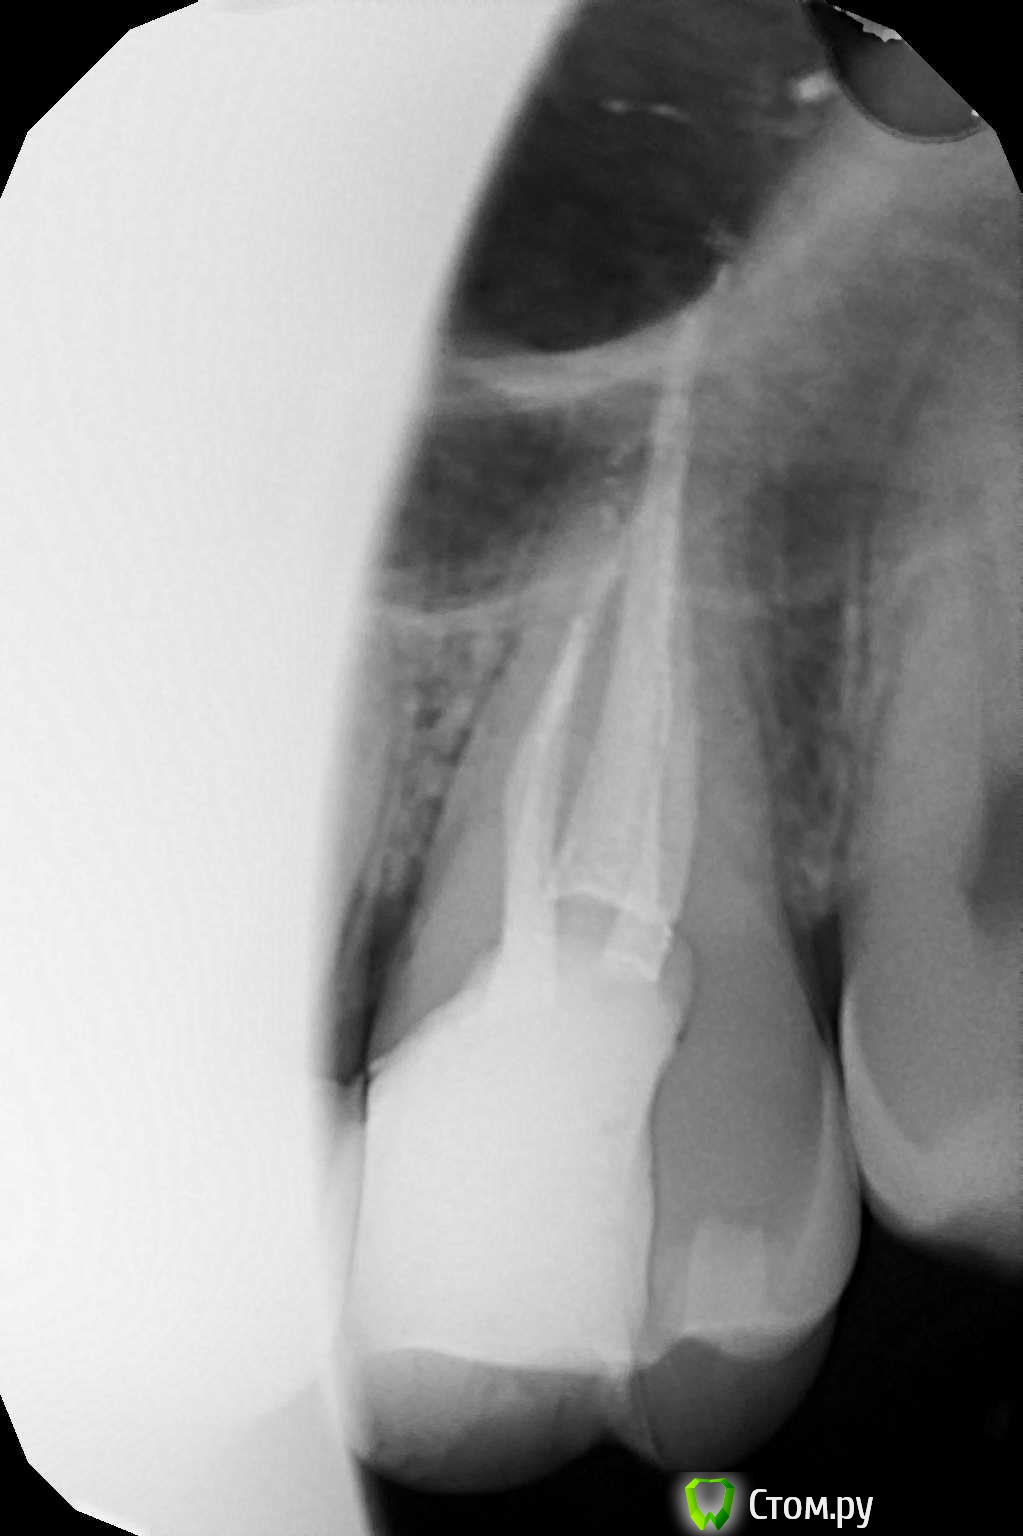

winnt Опубликовано 20 июля, 2014 Автор Поделиться Опубликовано 20 июля, 2014 red_butler, подскажите плиз еще по одному зубу, беспокоит уже больше года, два раза делали эндо, теперь вот иду в пятницу на его удаление (думаю все проблемы из-за выведенного силера) Периодически болит, перкуссия слабоболезненная (особенно со стороны неба) в щеке над ним часто как будто тяжесть или покалывания, утром чувство что есть припухлость в щеке над этим зубом. При пальпации со стороны в сторону зуба - чувство стягивания в щеке усиливается.Спасибо. Ссылка на комментарий

winnt Опубликовано 20 июля, 2014 Автор Поделиться Опубликовано 20 июля, 2014 Забыл добавить, после повторного эндо симптомы пропали на две недели, а потом усилились Ссылка на комментарий

red_butler Опубликовано 20 июля, 2014 Поделиться Опубликовано 20 июля, 2014 Снимки не информативны, выложите срезы Кт в других плоскостях Ссылка на комментарий

winnt Опубликовано 20 июля, 2014 Автор Поделиться Опубликовано 20 июля, 2014 (изменено) Вот еще пару снимков:Видео: видео_1 , видео_2 Изменено 20 июля, 2014 пользователем winnt Ссылка на комментарий